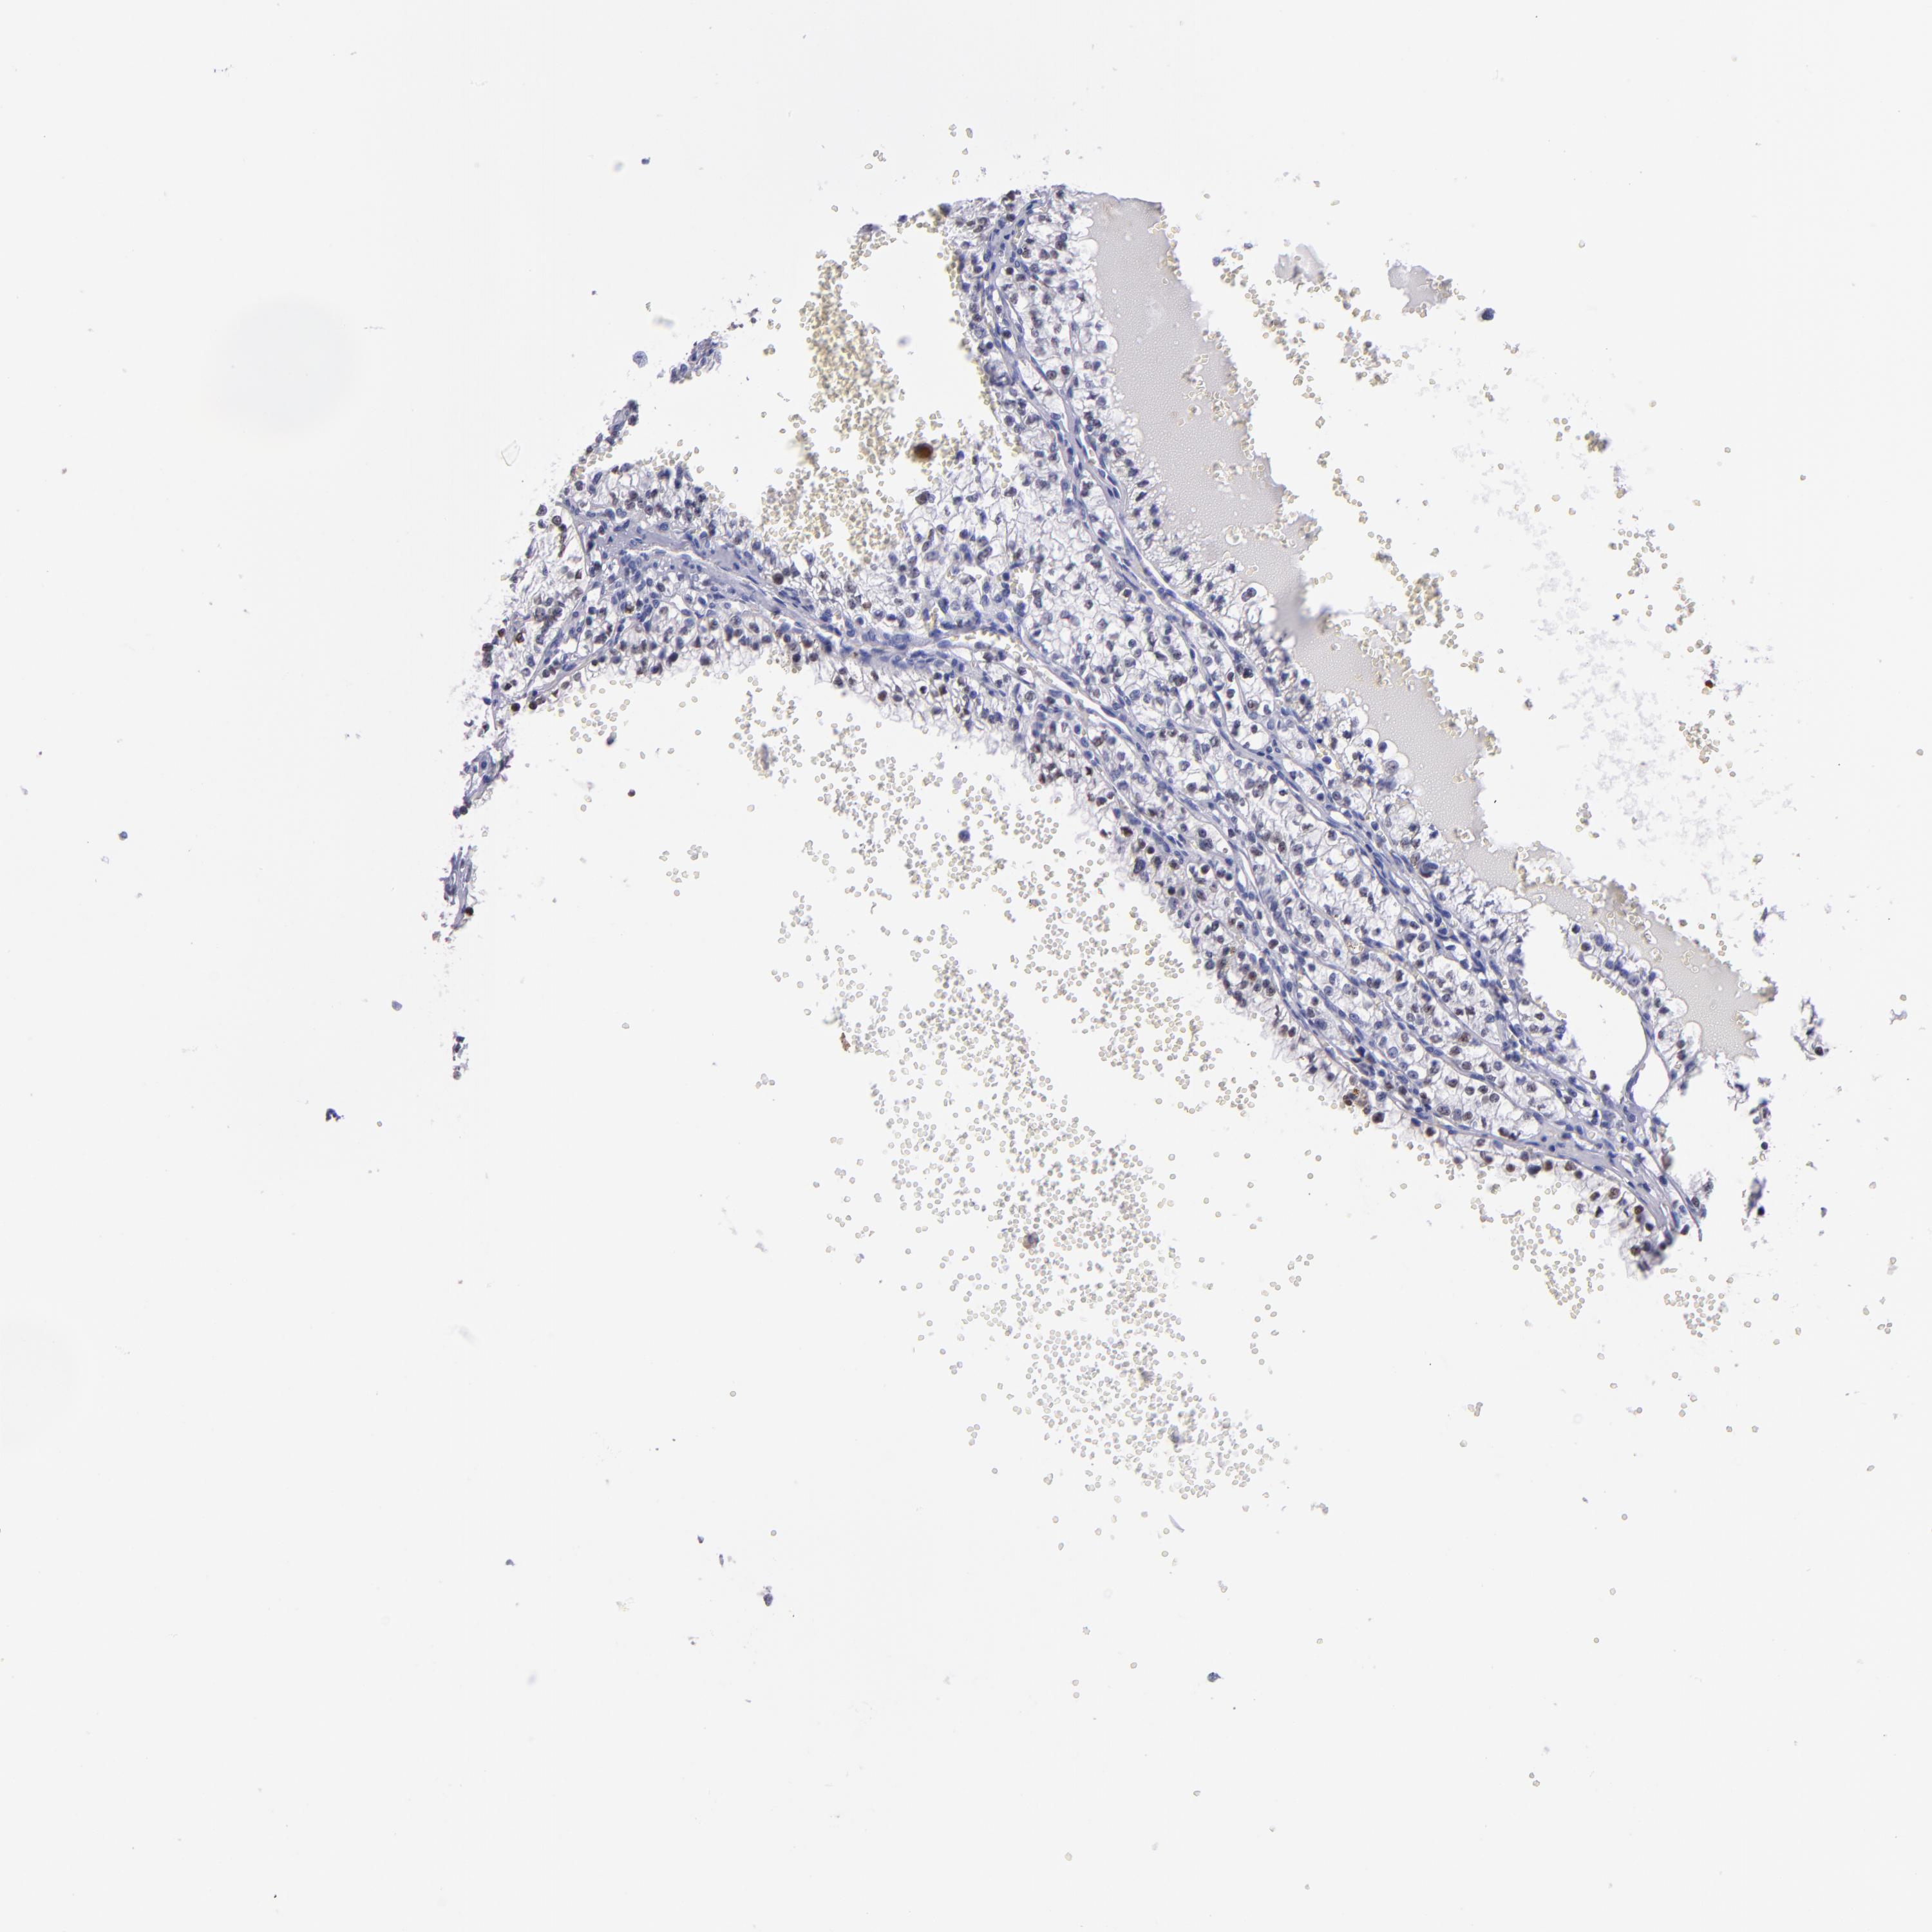

KIDNEY RENAL CLEAR CELL CARCINOMA (TCGA) - Interactive survival scatter ploti

The Survival Scatter plot shows the clinical status (i.e. dead or alive) for all individuals in the patient cohort, based on the same data that underlies the corresponding Kaplan-Meier plots. Patients that are alive at last time for follow-up are shown in blue and patients who have died during the study are shown in red.

The x-axis shows the expression levels (FPKM) of the investigated gene in the tumor tissue at the time of diagnosis. The y-axis shows the follow-up time after diagnosis (years). Both axes are complimented with kernel density curves demonstrating the data density over the axes. The top density plot shows the expression levels (FPKM) distribution among dead (red) and alive patients (blue). The right density plot shows the data density of the survived years of dead patients with high and low expression levels respectively, stratified using the cutoff indicated by the vertical dashed line through the Survival Scatter plot. This cutoff is automatically defined based on the FPKM cutoff that minimizes the p-score. The cutoff can be changed by dragging the vertical line or by entering a cutoff value in the square labeled "Current cut-off".

Under the Survival Scatter plot the p-score landscape (black curve; left axis) is shown together with dead median separation (red curve; right axis). Dead median separation is the difference in median mRNA expression between patients who have died with high and low expression, respectively. It is calculated as follows: median FPKM expression of dead patients with high expression - median FPKM expression of dead patients with low expression. This is intended to aid the user in visually exploring custom cutoffs and the associated p-scores and dead median separation.

Individual patient data is displayed and can be filtered by clicking on one or more of the category buttons on the top of the page. Categories describing expression level and patient information include: high, low, alive, dead, female, male and tumor stages. The scale of the x-axis can be toggled between linear and log-scale by clicking on the "x log" button. Mouse-over function shows TCGA ID, patient information and mRNA expression (FPKM) for each patient.

& Survival analysisi

Kaplan-Meier plots summarize results from analysis of correlation between mRNA expression level and patient survival. Patients were divided based on level of expression into one of the two groups "low" (under cut off) or "high" (over cut off). X-axis shows time for survival (years) and y-axis shows the probability of survival, where 1.0 corresponds to 100 percent.

TG is not prognostic in Kidney Renal Clear Cell Carcinoma (TCGA)

Best expression cut offi

Based on the FPKM value of each gene, patients were classified into two groups and association between prognosis (survival) and gene expression (FPKM) was examined. The best expression cut-off refers the FPKM value that yields maximal difference with regard to survival between the two groups at the lowest log-rank P-value. Best expression cut-off was selected based on survival analysis .

When clicking on this number, the vertical dashed line indicating cut-off, the interactive survival plot, and the Kaplan-Meier curve will be adjusted to show results based on the best expression cut-off.

: N/A

TCGA RNA samplesi

RNA-seq data is reported as average FPKM (number Fragments Per Kilobase of exon per Million reads), generated by the The Cancer Genome Atlas (TCGA) .

Normal distribution across the dataset is visualized with box plots, shown as median and 25th and 75th percentiles. Points are displayed as outliers if they are above or below 1.5 times the interquartile range. FPKM values of the individual samples are presented next to the box plot.

Average pTPM 0.9

Number of samples 521